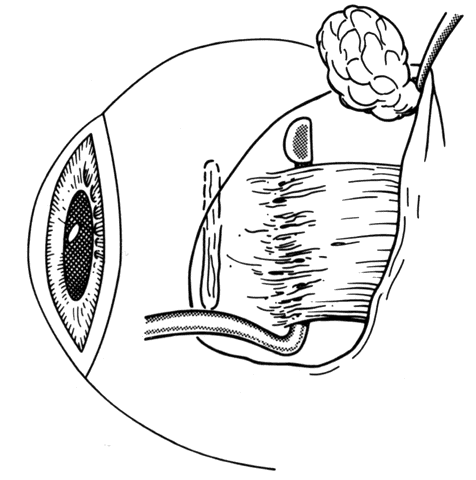

When approaching the superior and lateral rectus muscles that have had previous surgery, care should be taken to identify the superior oblique tendon and the inferior oblique muscles respectively. One should carefully free up attachments of these structures to the rectus muscle so that a normal anatomic relationship between the rectus and oblique muscles can be re-established. Frequently, the lateral rectus muscle will have adhesions to the orbital surface of the inferior oblique muscle as it passes underneath the lateral rectus. There is a propensity for the inferior oblique muscle to be drawn up into the insertion during resection procedures.37 When this occurs, the inferior oblique and lateral rectus muscle must be separated, and the inferior oblique muscle should be repositioned into its normal anatomic position (Figs. 30 through 33).

Fig. 30. To break posterior adhesions between the rectus muscle and the sclera, a second Jameson hook should be carefully pushed posteriorly along the belly of the rectus muscle. These adhesions are usually broken with little effort. If the adhesions resist blunt separation, a suture should be placed through the tendon and the muscle cut free from the insertion. With a malleable retractor, the adhesion is identified and then cut.

Fig. 31. The inferior oblique muscle has been incorporated into the insertion of the right lateral rectus.

Fig. 32. Sharp and blunt dissection is used to “free up” the inferior oblique muscle from the scleral side of the lateral rectus.

Fig. 33. If the dissection needs to be carried beyond the equator, care must be exercised to avoid avulsing or cutting a vortex vein. If this happens, a moderate hemorrhage will occur.